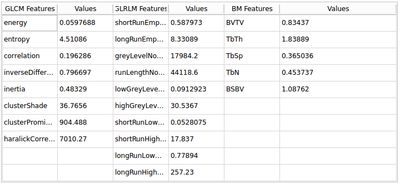

This extensions contain several modules that can be used to compute feature maps of N-Dimensional images using two well-known texture analysis methods: the study of Grey Level Co-occurrence Matrix (GLCM) and the study of Grey Level Run Length Matrix (GLRLM). The main algorithms used in this extension are part of a remote module of ITK called itkTextureFeatures Key Features:

Texture features

- BoneTexture

- ComputeGLCMFeatures

- ComputeGLRLMFeatures